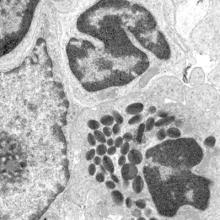

Immune System

Normal mesenteric lymph node

Lymph Node, Mesenteric

Normal spleen

Spleen

Normal thymus

Thymus